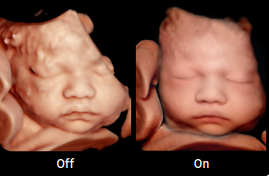

• Recursos exclusivos em 3D: RealisticVue™, CrystalVue™, PortraitVue™, Luminant™.

Imagens Clínicas